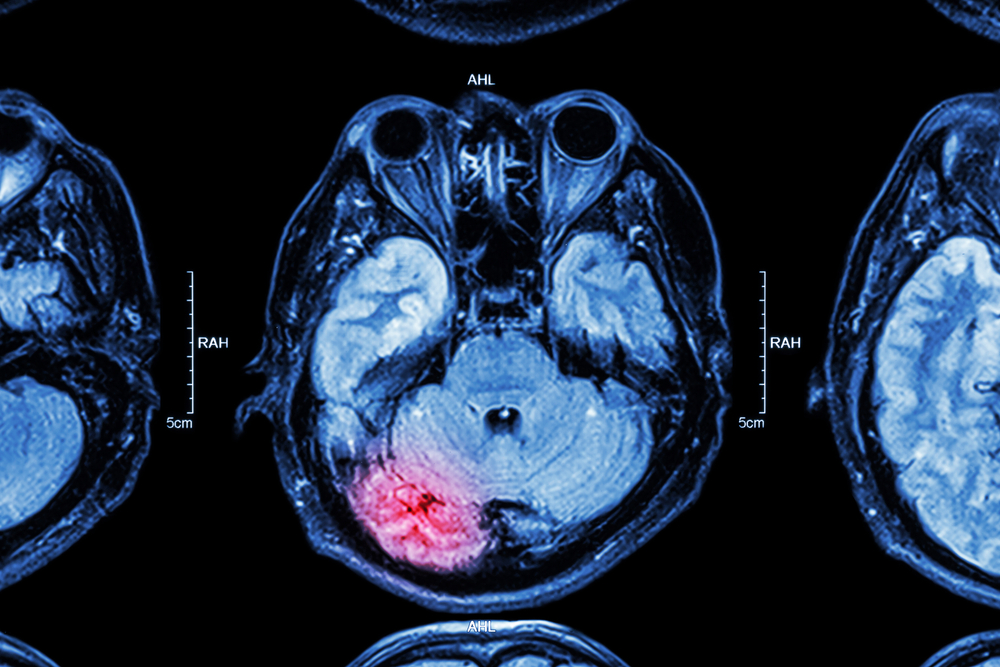

Administrarea de acid tranexamic, un medicament disponibil şi ieftin, imediat după o lovitură la cap opreşte hemoragiile cerebrale şi poate salva viaţa pacienţilor, arată un studiu clinic amplu realizat la nivel internaţional.

Potrivit autorilor studiului, care a inclus circa 12.000 de pacienţi, acidul tranexamic opreşte hemoragiile din creier şi din preajma acestuia dacă se produc rupturi la nivelul vaselor de sânge.

Medicamentul împiedică destrămarea cheagurilor de sânge – el nu repară daunele produse, ci împiedică agravarea situaţiei din cauza hemoragiilor cerebrale.